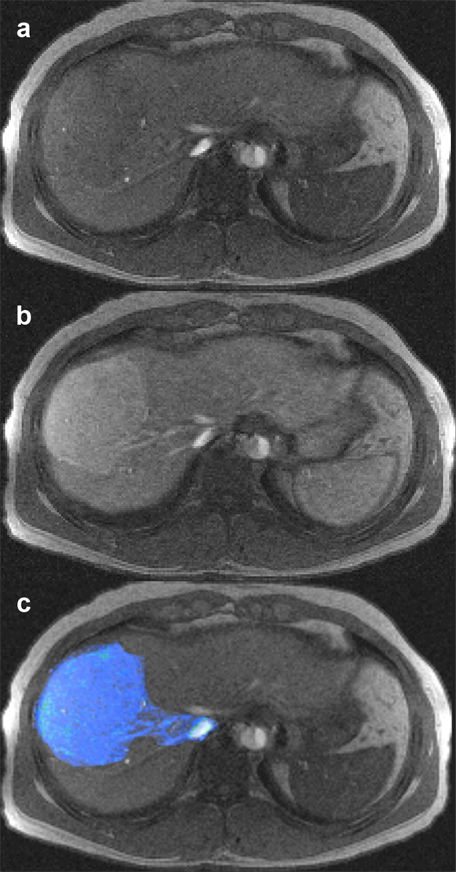

Figure 15-08:

Multichannel images: (a) plain image of a liver, (b) contrast-enhanced liver, with depiction of focal no­du­lar hyper­pla­sia, part of a dy­na­mic series, and (c) overlay (superposition) of enhanced lesion on plain liver im­age.